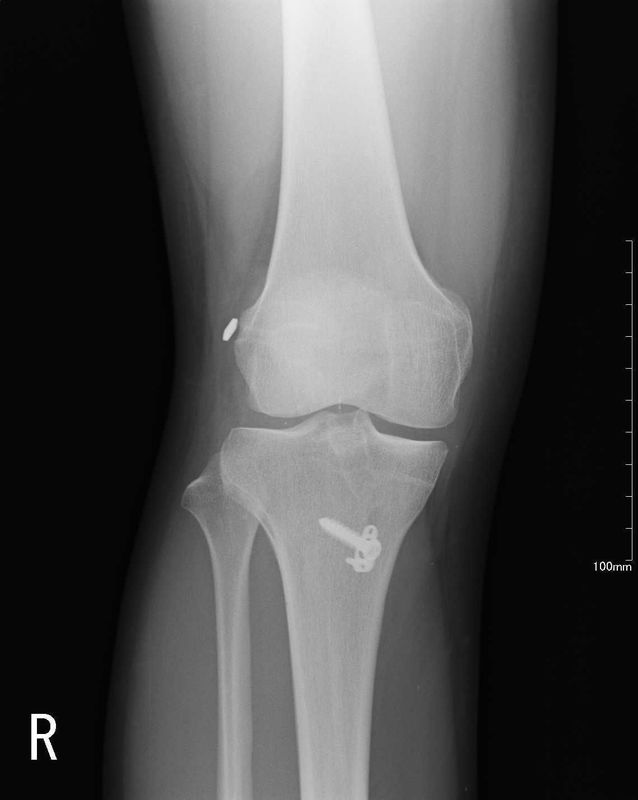

術前画像

| レントゲン | MRI |

![]() | ![]() |

| 骨傷なし、関節変形なし | ACLの連続性や緊張がみられない |